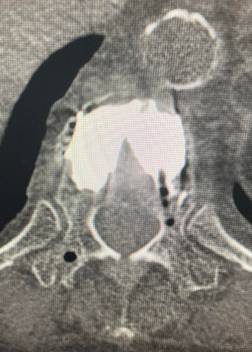

頚椎前方固定術

頚椎の手術方法には大きく分けると、前方から行う方法(前方法)と後方から行う方法(後方法)があります。

前方法は頚部に横方向(もしくは斜め方向)の小切開を加え、気管、食道、血管などの大事な臓器を避けながら、脊髄圧迫の原因となっている椎間板ヘルニアや骨棘(こつきょく)を取り除き、神経の圧迫を直接取り除く方法です。

摘出した椎間板のスペースにはケージといわれる代替物を挿入します。手術機器、技術の進歩により術後の安静や装具着用期間が短縮され、入院期間も短縮しております。

後方法と異なり頚椎の後方の筋肉組織を損傷しないため、術後に生じうる頚部痛を最小限にとどめることが期待できます。

対応としている疾患には頚椎椎間板ヘルニア、頚椎後縦靭帯骨化症、頚椎症性脊髄症、頚椎症性神経根症などがあります。当院ではすべての頚椎の疾患に対して前方法を行っているわけではありません。外来で担当医師にご相談ください。